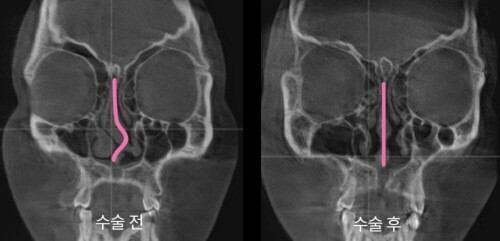

| ▲휘어있는 비중격과 수술 이후 곧아진 비중격 모습. (사진=아이디병원 제공) |

아이디병원은 대학병원에서 사용하는 첨단 3D-CT를 통한 정확한 검사와 이비인후과 및 성형외과, 마취통증의학과 등 전문의 협진을 통해 당일 한 번에 모든 과정을 수술하는 시스템을 구축했다. 코 외관(골절된 코뼈 교정)과 코 내관(휘어진 비중격 교정)을 각 전문의가 협진으로 수술하는 형태를 구축한 것.